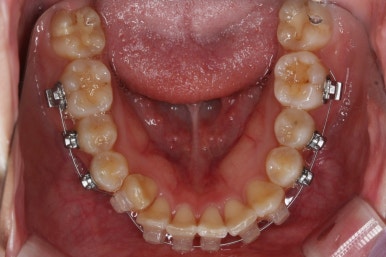

위 사진은 연산동교정치과 처음 내원하셨을 때의 입안 모습입니다. 몇 가지 모습이 관찰됩니다.

치아가 삐뚤삐뚤합니다.

위~아래 앞니가 많이 겹쳐서 아랫니가 많이 모이지 않는 "과개교합" 입니다.

앞니가 앞으로 뻐뜨러져 있습니다.

아랫니도 어느 정도 많이 가지런해졌습니다.